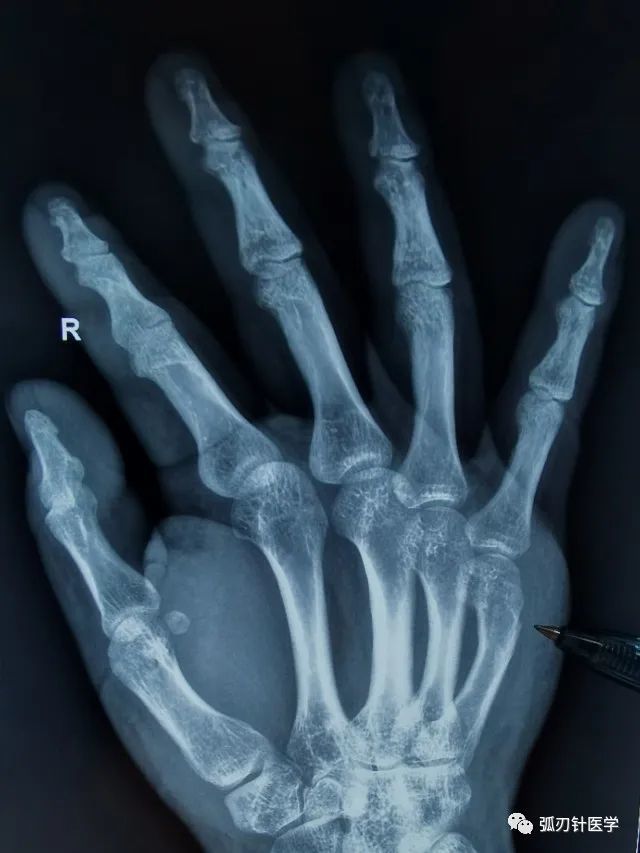

小指近节指骨骨折手术治疗 医联

手指粉碎性骨折图片 第1页 一起扣扣网